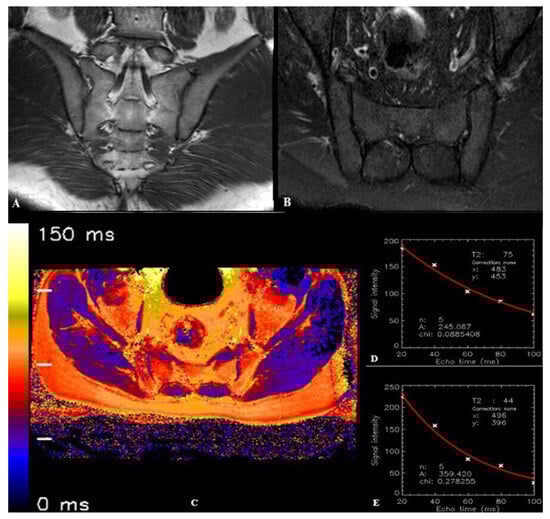

| T2 relaxation time—bone (ms) *, (Mean ± SD) | 100.23 ± 7.41 | 69.44 ± 4.37 | <0.001 |

| T2 relaxation time—cartilage (ms) **, (Mean ± SD) | 44.0 ± 3.19 | 43.2 ± 3.41 | 0.249 |